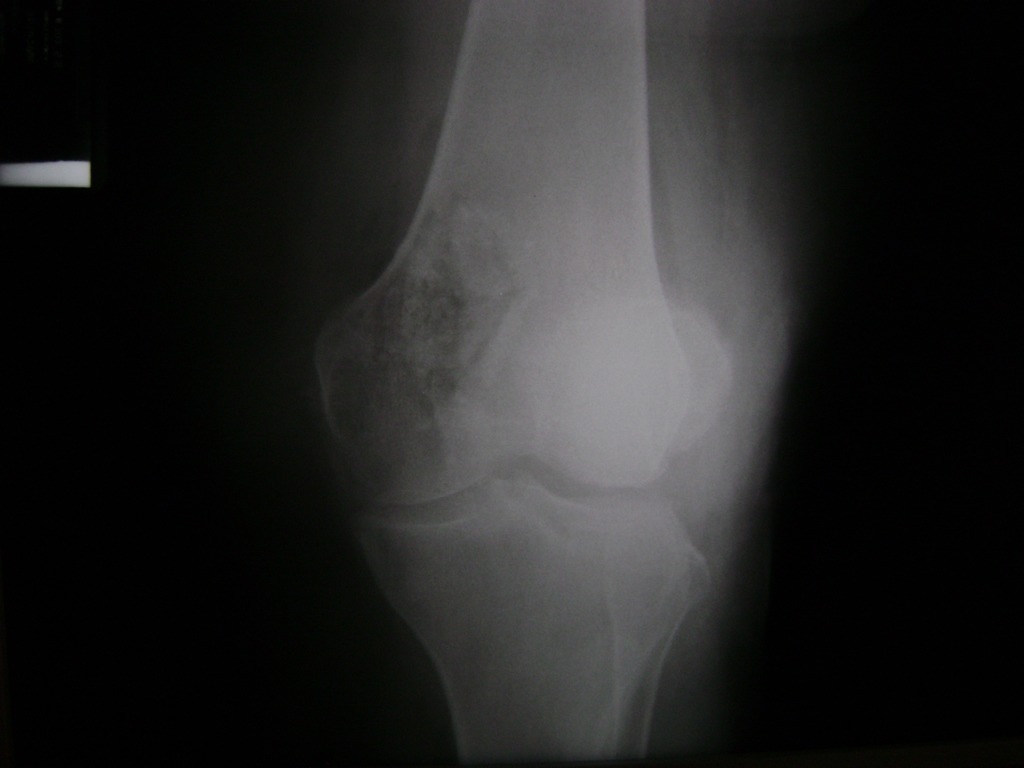

Cirugías de Rodillas

La artroscopia de rodilla es un cirugía en el cual la estructura interna de la articulación es examinada ya sea para realizar un diagnostico o para realizar un tratamiento, este procedimiento se realiza utilizando un instrumento parecido a un pequeño tubo llamado artroscopio.